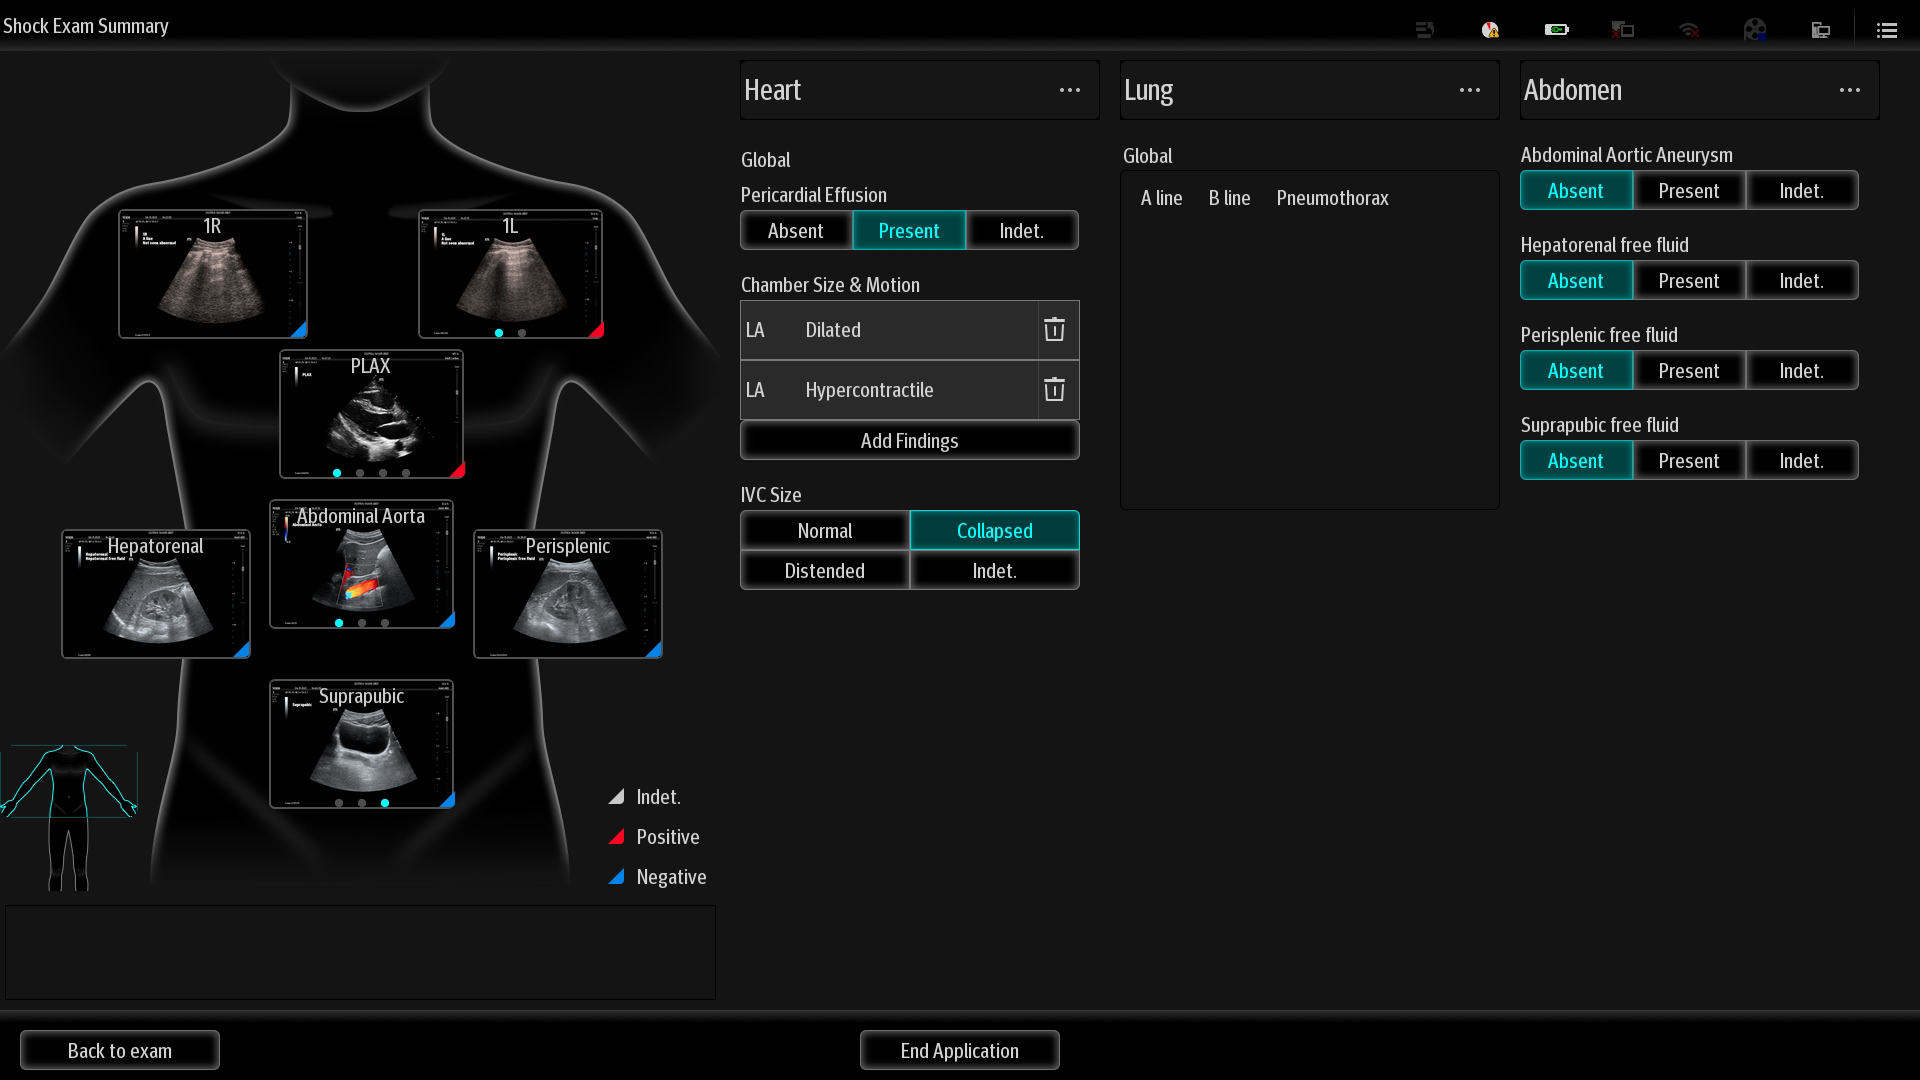

Mindray's Emergency Ultrasound Solutions address clinical challenges through a systemic approach. Those solutions cover the entire emergency care process from pre-hospital rescue and ambulance transport to ER treatment and in-hospital transfer. The versatility of Mindray Ultrasound shaping from Tablet system, Laptop-based system to Handheld Ultrasound system brings up the power of Ultrasound at the point of care. Clinical oriented smart features and protocols assist decisions with confidence.